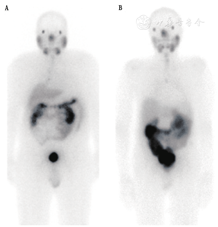

2.配体。目前,临床报道的用于177Lu的RLT主要有2种PSMA配体:一种是最早被Heidelberg研究组发现的177Lu-PSMA-617[29],是目前绝大多数研究中心使用的配体[9,10,11,12,14,16,17,18];另一种是由Wester研究组首次报道的177Lu-PSMA I&T(显像和治疗)[30]。2种配体对PSMA都有很高的亲和力(nmol级),且在前列腺癌细胞中有较强而持久的聚集。2种配体的生物分布极为类似,在肾脏、泪腺、唾液腺和近端小肠中有较高的生理性摄取(图1)。

主要受辐射照射的器官包括:肾脏(0.5~0.8 Gy/GBq,保守剂量限值23 Gy[31])、泪腺和唾液腺(0.6~1.4 Gy/GBq,剂量限值未确定[31])[8,10,11,12,17,32]。骨髓(0.05 Gy/GBq)[8,11,12,17]和肝脾(均0.5 Gy/GBq)[12,17,32]中的辐射剂量远低于临界值。